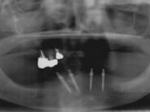

術前術前骨の高さが不足している場合、通常のインプラントでは処置が不可能なものが多い。特殊なショートインプラントを用いて可能になる例。 術前 術前CT像術前CT像術前CT像、下歯槽神経が下あごの中央部を走行しているため利用できる骨の高さが少ない。 埋入予定計画埋入予定計画埋入予定計画 術後レントゲン術後レントゲン、ひだりは少し神経をおそれすぎてやや埋入深度が不足、しかしこれでもしっかりと骨と固着した。